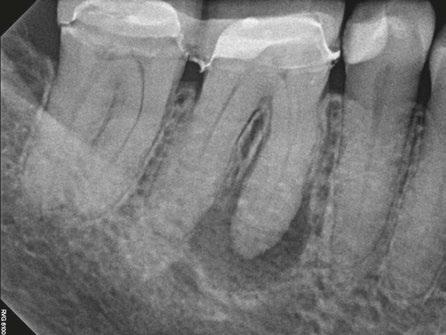

The patient was anesthetized with topical benzocaine and 3.4mL Septocaine (Articaine hydrochloride 4% and epinephrine 1:100,000) (Septodont, Saint-Maur-Fosses, France) via buccal and lingual infiltration. A rubber dam was placed, and the root canal system was accessed through the crown. Working length was obtained with Root ZX II apex locator (J. Morita, Kyoto, Japan) and verified with a periapical radiograph to be 24 mm. The tooth was then mechanically instrumented with WaveOne® rotary files (Dentsply Sirona, Charlotte, North Carolina) using 10mL of 6% NaOCl throughout the procedure. A final irrigation with EDTA (3mL) and SmartLite Pro EndoActivator™ (Dentsply Sirona, Charlotte, North Carolina) for 1 minute, followed by 6% NaOCl and activator for 1 minute was completed prior to obturation. Obturation was performed with EndoSequence® BC sealer (Brasseler

6A-6D: 6A. Preoperative periapical radiograph of

proper working

radiograph of tooth No. 11 confirmed proper master cone

periapical radiograph of tooth No. 11 verified length control and appropriate obturation

Figures

tooth No. 11. 6B. Periapical radiograph of tooth No. 11 confirmed

length. 6C. Periapical

fit. 6D. Postoperative

USA, Savannah, Georgia) and gutta percha via continuous wave condensation. EndoSequence BC liner blue (Brasseler USA, Savannah, Georgia) was placed over the gutta percha at the canal orifice, and the tooth was temporized using a cotton pellet and Fuji IX placed in the access (Figure 6). Following completion of the root canal, the patient was scheduled for a 3-month reevaluation and referred to her provider for definitive restoration. Healing was observed at the 3- and 6-month postoperative visits. Periapical radiographs were exposed at each visit revealing bony healing (Figure 7). The patient reported no pain or symptoms following nonsurgical root canal treatment. At both visits, percussion and palpation were negative. A CBCT was captured at the 6-month postoperative exam to evaluate healing. Coronal CBCT slices revealed a reduction in lesion size to 3.5 mm x 1.6 mm. Sagittal slices also showed reduction in lesion and maintained health of bone surrounding implant No. 12 (Figure 8). A 2011 article by Ng outlines eleven factors that, if present, improve periapical healing following primary non-surgical root canal treatment.17 Only two of these eleven factors, absence of a preoperative periapical lesion and size of the preoperative periapical lesion, were not met in this case report. Along with this and the 2017 AAE Treatment Options for the Compromised Tooth: A Decision Guide article, the final prognosis for healing is favorable.16

Figures 7A-7C: 7A. Immediate postoperative periapical radiograph. 7B.Periapical radiograph of tooth No. 11 at the 3-month reevaluation showing a reduction in size of the periapical radiolucency. 7C. Periapical radiograph of tooth No. 11 at the 6-month reevaluation showing a further reduction in the size of the periapical radiolucency.